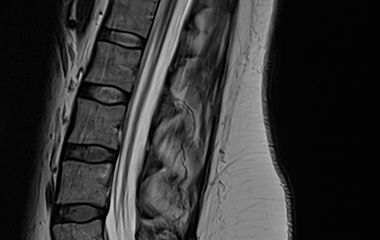

Der Bereich Hydrozephalus, Chiari-Malformation und Tethered-Cord-Syndrom umfasst die Diagnostik und Behandlung komplexer Erkrankungen des Liquorsystems sowie des Gehirns und Rückenmarks. Wir behandeln angeborene und erworbene Formen des Hydrozephalus, einschließlich des Normaldruckhydrozephalus, der sich häufig durch Gangstörungen, kognitive Veränderungen und Blasenfunktionsstörungen äußert. Ein weiterer Schwerpunkt ist die Chiari-Malformation, bei der es zu einer Verlagerung von Kleinhirnanteilen in den Spinalkanal kommen kann und die vielfältige neurologische Symptome verursachen kann. Das Tethered-Cord-Syndrom beschreibt eine krankhafte Fixierung des Rückenmarks, die sowohl in klassischer als auch in okkulter Form auftreten und zu Schmerzen, neurologischen Defiziten oder Funktionsstörungen führen kann. Ziel unserer Behandlung ist es, neuralen Strukturen zu entlasten, eine weitere Schädigung zu verhindern und die Lebensqualität der Patientinnen und Patienten zu verbessern. Grundlage hierfür sind eine präzise Diagnostik, individuell abgestimmte Therapiekonzepte und eine umfassende, verständliche Aufklärung.

Tethered-Cord

Bei Hydrozephalus bieten wir verschiedene Formen der Liquorableitung an, darunter den Liquorshunt und den ventrikuloperitonealen Shunt (VP-Shunt), individuell angepasst an die jeweilige Erkrankung. Als alternative, shuntunabhängige Therapie führen wir die endoskopische Drittventrikulozisternostomie (ETV) durch, sofern die anatomischen Voraussetzungen gegeben sind. Patientinnen und Patienten mit Arnold-Chiari-Malformation behandeln wir durch eine gezielte mikrochirurgische Dekompression, um den Liquorfluss zu verbessern und neurologische Symptome zu lindern. Beim Tethered-Cord-Syndrom, einschließlich okkulter Formen, setzen wir auf ein minimalinvasives Detethering zur schonenden Entlastung des Rückenmarks.